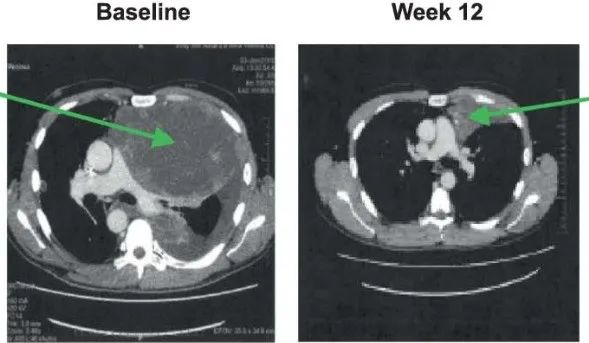

比如下面这位幸运的滑膜肉瘤患者,接受TCR-T治疗后,肺部的转移病灶显著消退劳力性呼吸困难症状也明显改善。